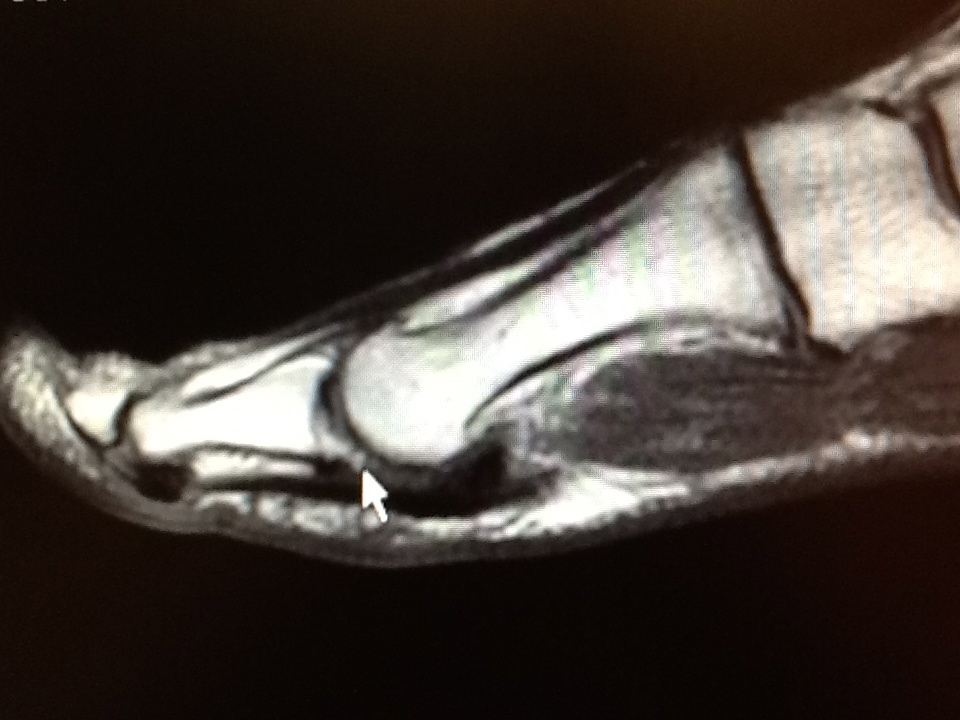

Sesamoiditis treatment 2020! [sesamoid bone pain & fracture fix]. Mri sesamoid foot fracture toe bone problems noted blake ankle richard dr irregularity base another metatarsal